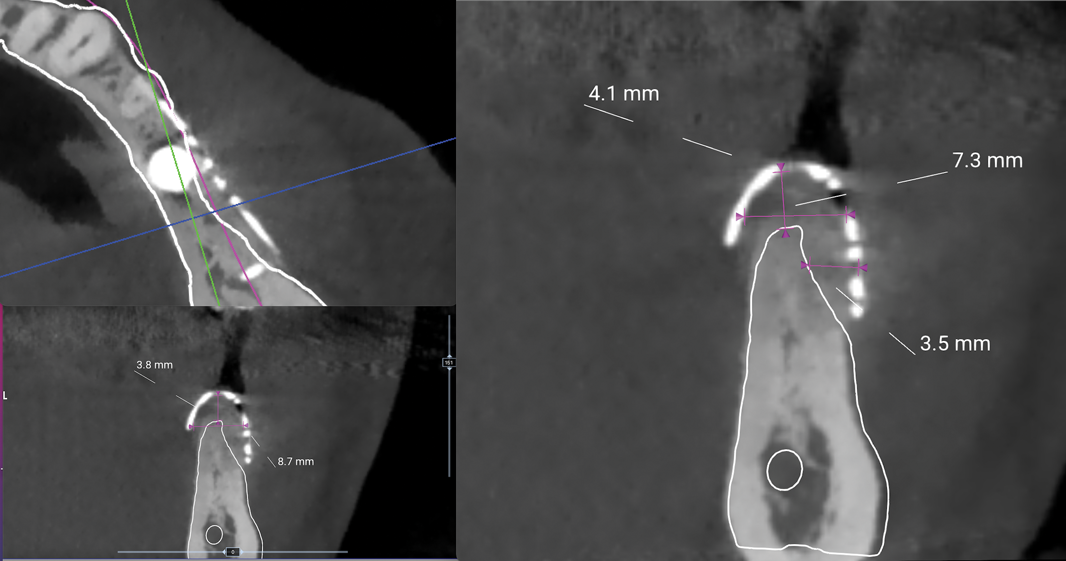

In each case, a CBCT was taken prior to mesh removal. Through the use of the measurement tool of the planning software, a calculation of the amount of bone gained was done. Patient 1 showed 4.1 mm vertical gain and a width of 8.7 mm (Figure 22). Patient 2 presented 6.7 mm vertical gain and a 10.8 mm width (Figure 23).

Fig 22. CBCT showing different gains of bone width before mesh removal, Patient 1.

Figure 22

Patient 1 was a 69-year-old man who was a former professional athlete. He developed heart issues, which led to the use of various medications, such as metoprolol, Ventolin, Seretide, pantoprazole, Rhinocort, and Eliquis. Based on a CBCT scan (Figure 1), the patient needed augmentation in the mandibular left jaw (Siebert class I). Radiographic examination revealed a periapical lesion present at site No. 20 as well as a very thin ridge width of only 3.7 mm in the posterior mandible. Implant planning was performed using planning software, and a custom-made titanium mesh was designed (Figure 2).12